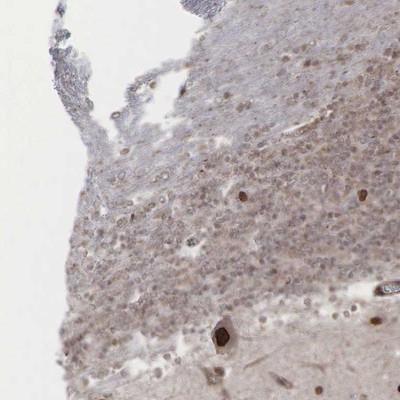

- Main image

- Experimental details

- Immunohistochemistry-Paraffin: GPRASP1 Antibody [NBP1-83391] - Staining of human cerebellum shows strong nuclear positivity in purkinje cells.